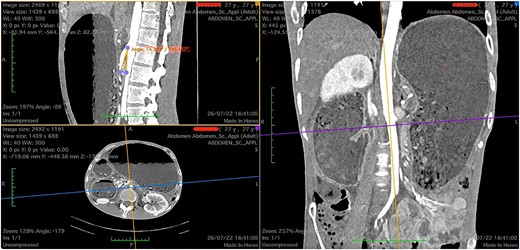

Upon admission, the patient was severely malnourished with a body mass index (BMI) of 15.7 kg/m2. On physical exam, his abdomen was softly distended and tympanic but non-tender. On chest auscultation, the patient had diminished breath sounds at the lower base of the right lung. He was transferred to the intensive care unit due to refractory shock and started on vasopressors and broad-spectrum antibiotics. A nasogastric tube was placed with an output of approximately 1.8 L of bilious content. After hemodynamic stabilization, computed tomography (CT) scan of the abdomen was performed, which revealed a distended stomach and first and second portion of duodenum (Fig. 1).

Computed tomography images showing a narrow aortomesenteric angle of 14.3° (sagittal section) and a massively dilated stomach, as seen on coronal and axial sections.